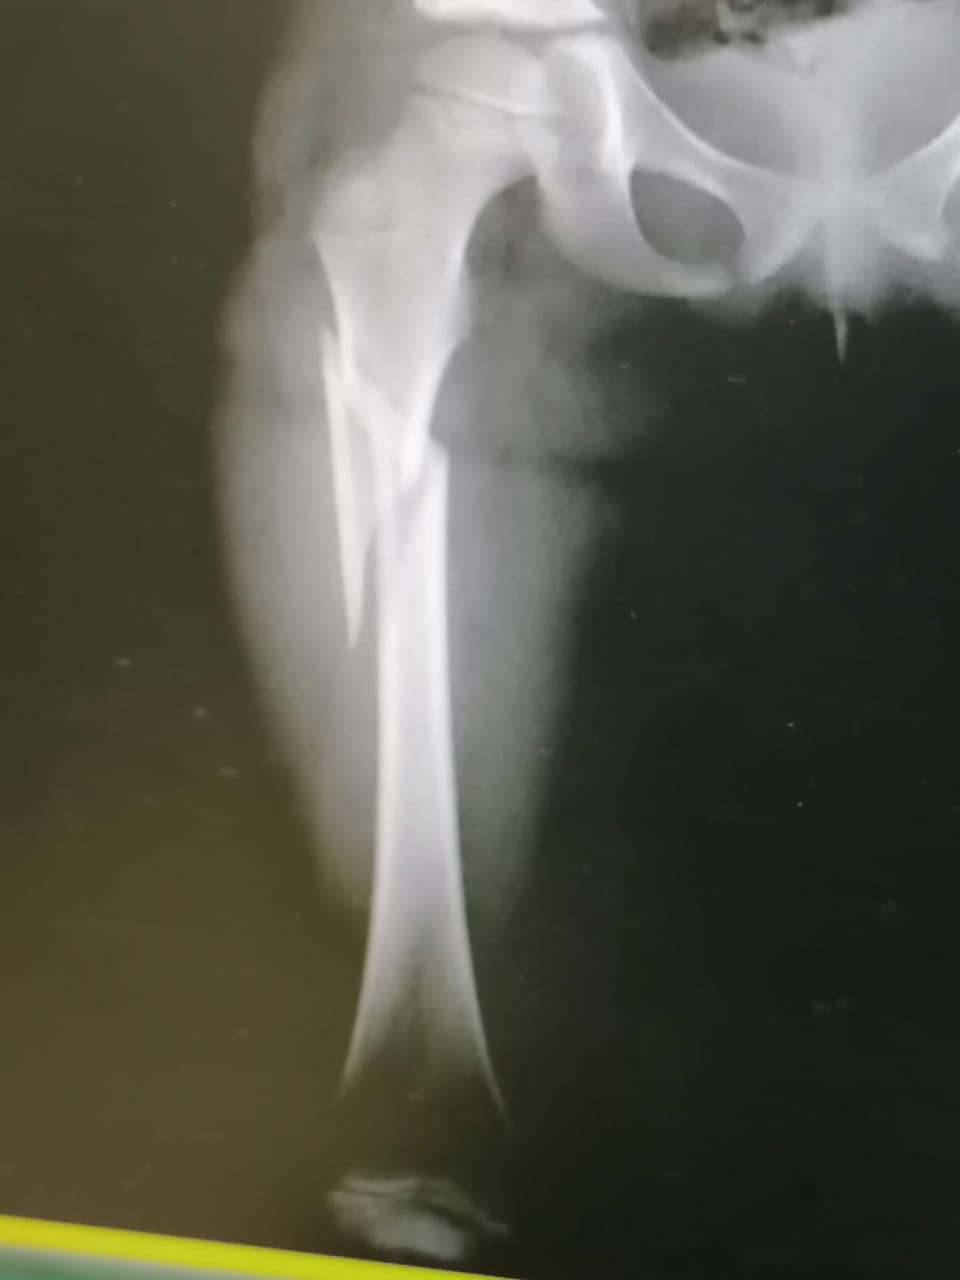

الانسان أغلى ما نملك عبارة أطلقها المغفور له باذن الملك الحسين على ابناء شعبه بصفة عامة ولكن ما حدث في مساء يوم الجمعة الماضي للطفلة ليان ينفي هذه المقولة ويلخص بان الانسان الفقير أرخص شيء قي هذا الوطن فقد هزت فاجعة في حي الملك عبدالله في صافوط تقشعر لها الضمائر الحية حيث انقلبت حاوية من نوع الهزاز وغير مثبتة على الارض وكانت ممتلئة بأطنان من النفايات حيث ان الطفلة ليان كانت تحاول القاء كيس القمامة في وسط الحاوية وليس على الارض كعادة بعض الاطفال ولكن لسوء حظ ليان كانت بعض القطط متواجدة في الحاوية كالعادة فقامت قطة بالقفز من الحاوية مما ادى لانقلابها على الطفلة الصغيرة ذات الست سنوات حيث غدت الحاوية تغطي جسدها الغض مما سبب لها كسور كبيرة في الحوض والقدم وتم اسعافها لمسشفى الامير حسين حيث تم اجراء عملية زرع اسياخ وبراغي في جسدها الصغير كل هذا لم يهز شعرة في ضمائر المسؤولين حيث ان ذوي الفتاة لم يتلقوا اي أتصال حتى بالهاتف وهذه استهانة كبيرة بحياة البشر وخاصة الفقراء وذويها ليست لديهم الامكانيات لدفع تكاليف علاج ابنتهم الصغيرة حيث ان علاجها مكلف